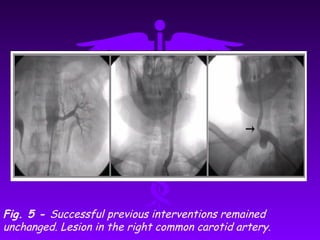

Fig. 5 - Successful previous interventions remained

unchanged. Lesion in the right common carotid artery.

Fig. 5 -Successful previous interventions remained unchanged. Lesion in the right common carotid artery.